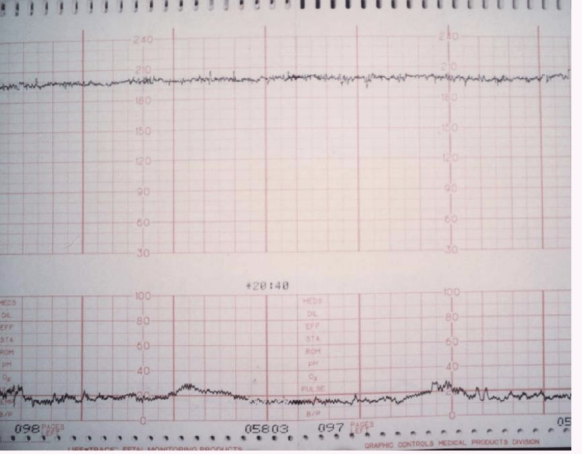

Absent: Undetectable; associated with risk for fetal metabolic acidemia, requires prompt evaluation.

Absent Variability: No detectable changes in fetal heart rate; typically associated with fetal distress and requires immediate evaluation. NEVER WANT TO SEE STRAIGHT LINES!!!!!

Bradycardia: Baseline < 110 bpm for > 10 minutes

profound bradycardia (< 60 bpm) is an emergency (CPR).